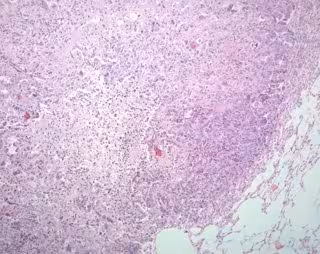

Investigadores de varias de las principales universidades de Estados Unidos y la Universidad ITMO, en Rusia, han identificado una serie de nuevas mutaciones conductoras en células de cáncer de pulmón que pueden ser sensibles a las terapias dirigidas genómicamente y a la inmunoterapia. Como se detalla en un artículo publicado en 'Nature Genetics', los autores examinaron 1.144 perfiles genómicos de cánceres de pacientes con dos de los tipos más comunes de tumores de pulmón: adenocarcinoma de pulmón y carcinoma de pulmón de células escamosas.

En total, los científicos han detectado 38 genes mutados de manera significativa en adenocarcinoma de pulmón y 20 en carcinoma de pulmón de células escamosas. Sin embargo, sólo seis genes mutados fueron compartidos por los dos tipos de tumores lo que sugiere que, aunque se dan ambos tipos en el mismo órgano, difieren de forma significativa entre sí.

El cáncer de pulmón es el cáncer más común en todo el mundo líder en la cantidad de muertes. Cada año, se registran más de 1,5 millones de casos de cáncer de pulmón, de los cuales el 85 por ciento pertenecen al cáncer de pulmón de células no pequeñas, que está representado principalmente por dos subtipos: adenocarcinoma de pulmón y carcinoma de células escamosas de pulmón. Pueden surgir de los diferentes factores ambientales o procesos biológicos, pero fumar no siempre es la causa principal.